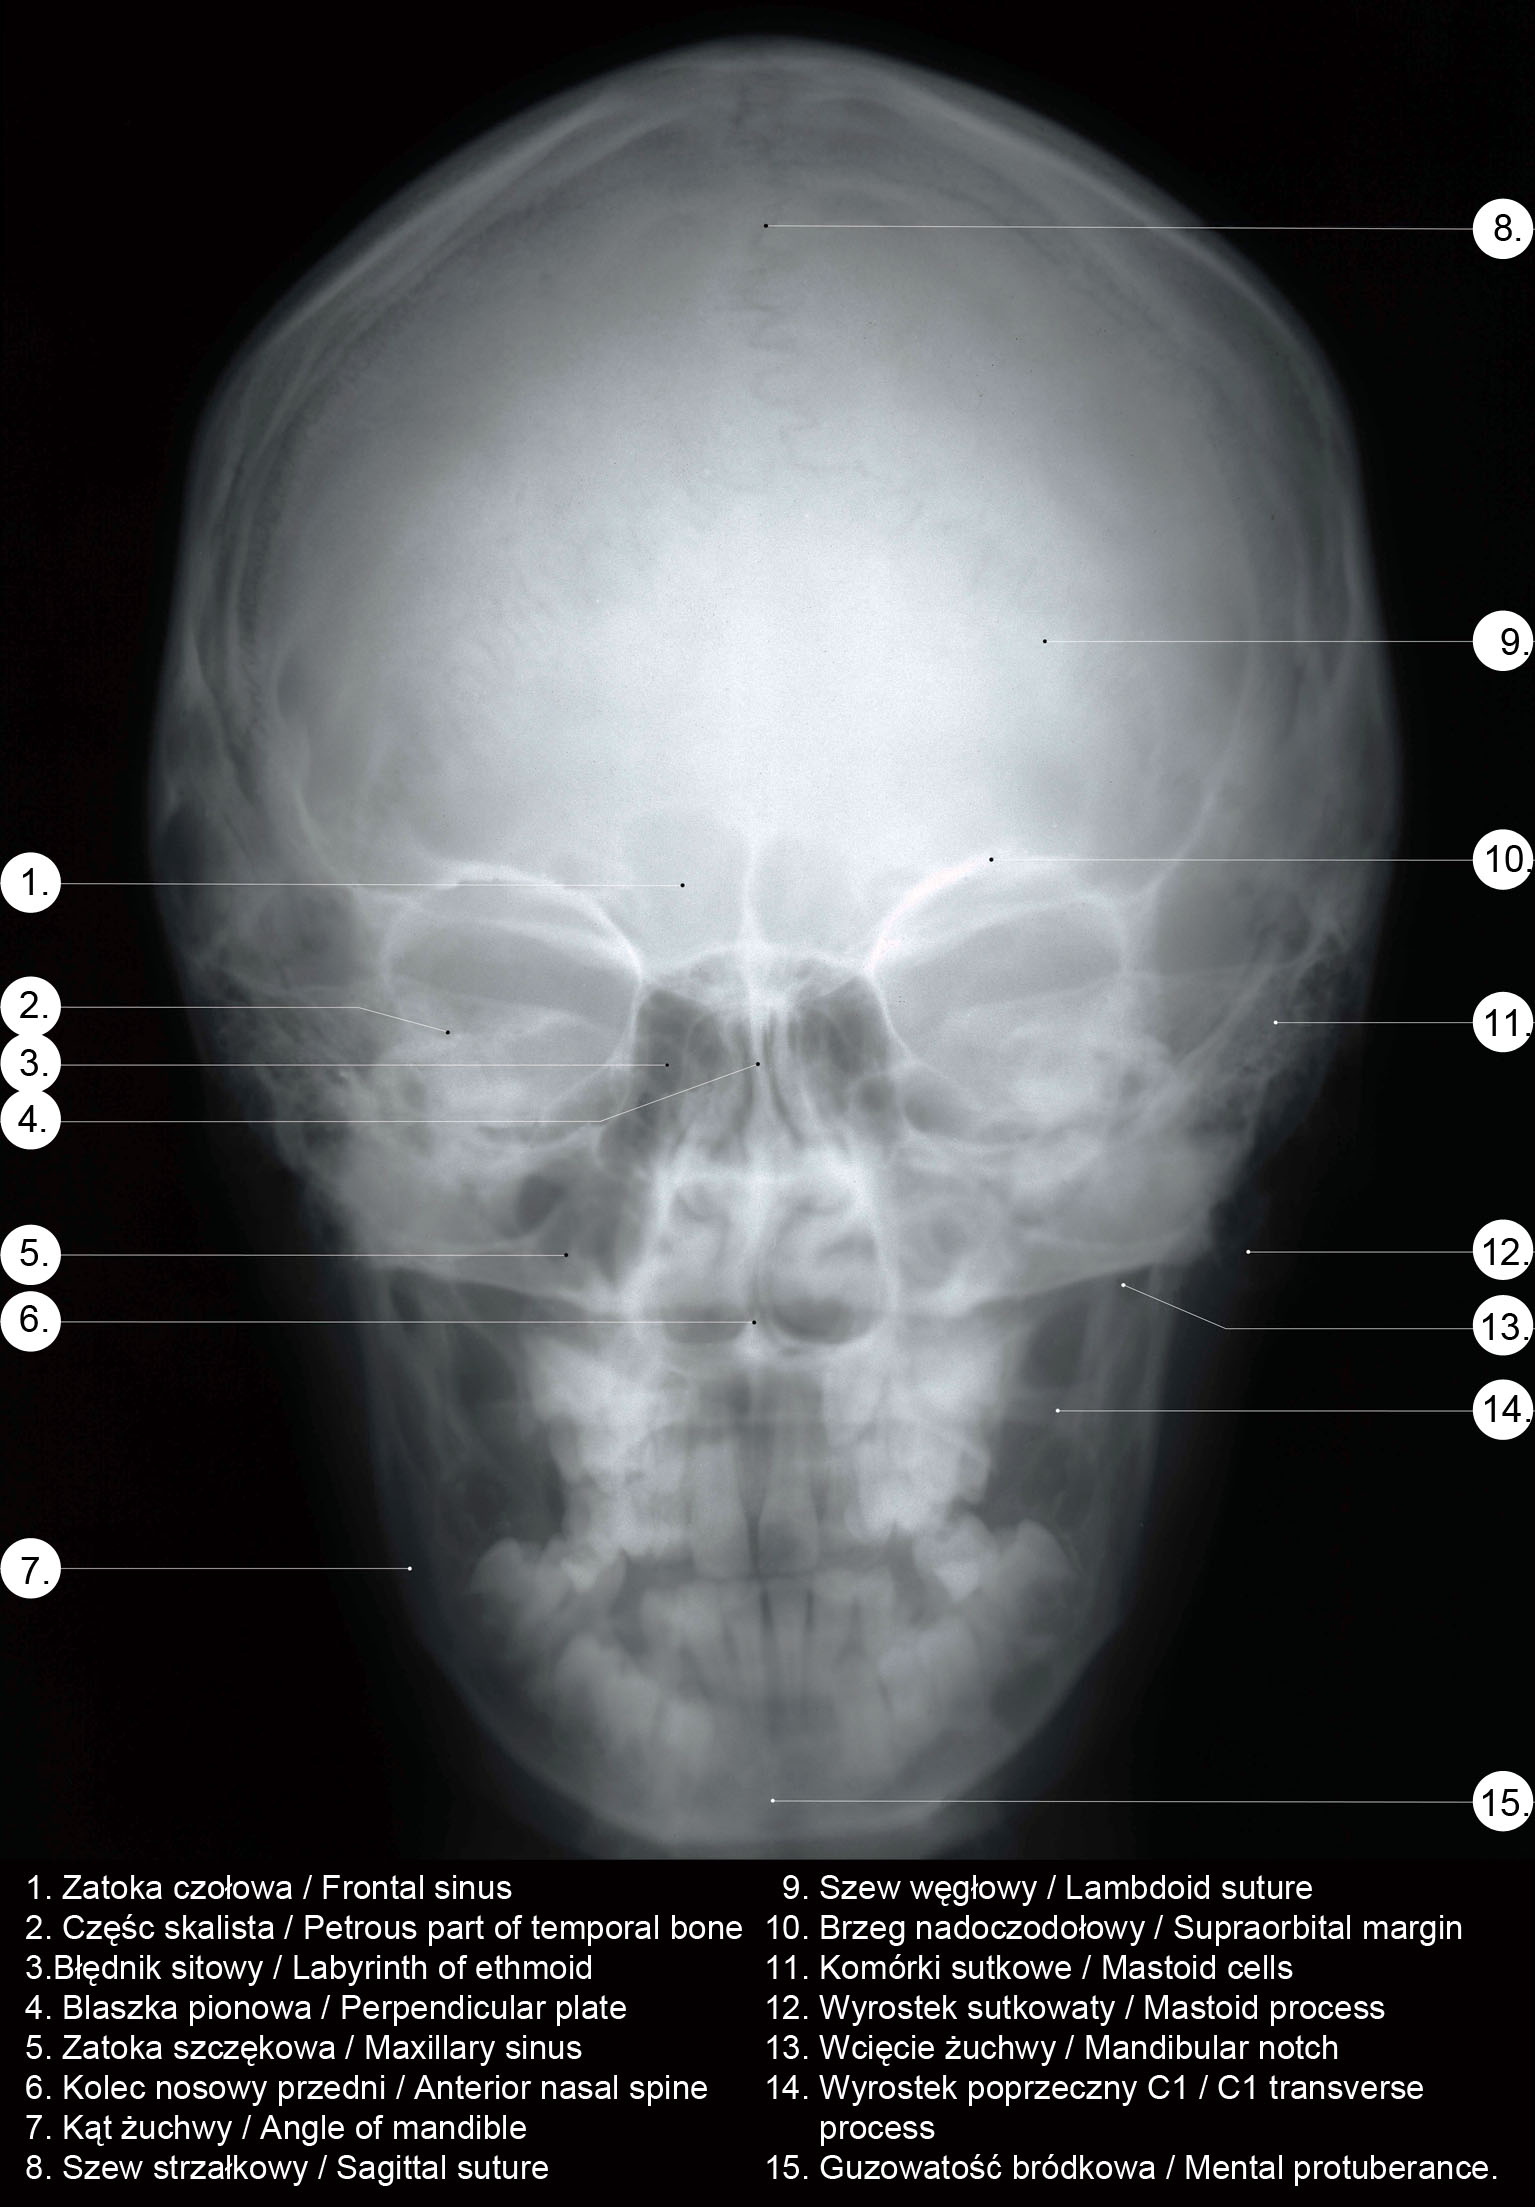

RTG głowy frontalny.

RTG głowy boczny.

RTG głowy od góry.

. RTG głowy człowieka.